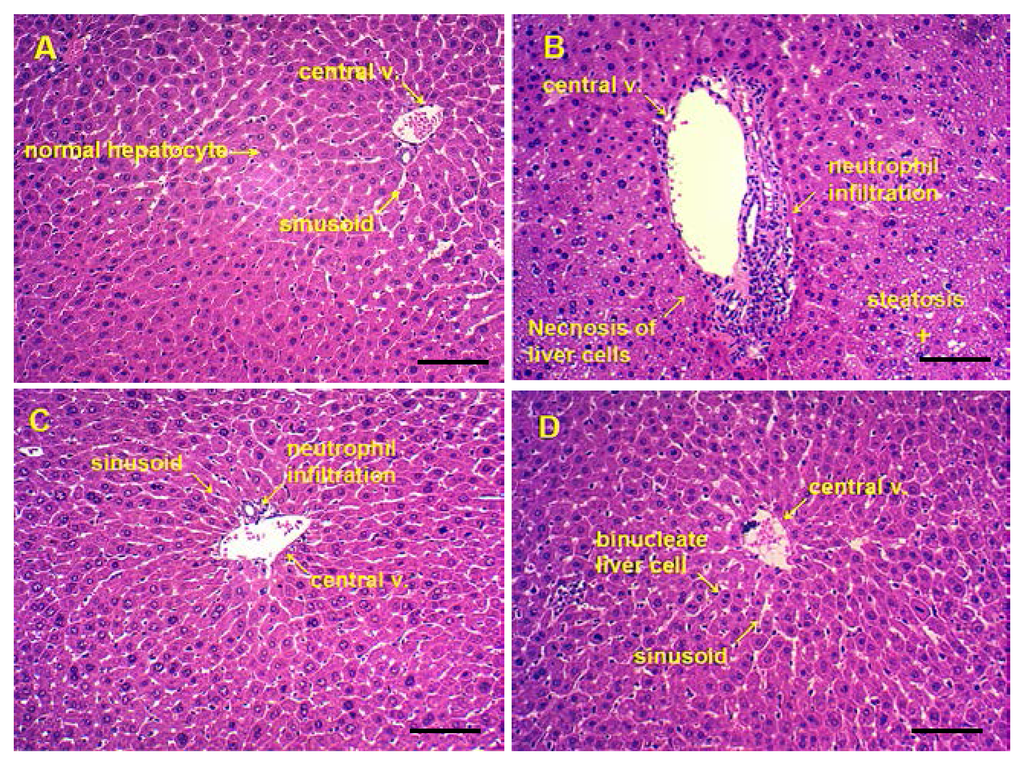

3.6. Pathological Observations and Steatosis Grade

| Groups | Dosage (mg/kg) | Steatosis Grade | Score | Ridit | ||||

|---|---|---|---|---|---|---|---|---|

| 0 | I | II | III | IV | ||||

| Normal | 4 | 3 | 1 | 0 | 0 | 5 | 0.348 | |

| Alcohol | 0 | 1 | 2 | 3 | 2 | 19 | 0.835 * | |

| Alcohol + Silymarin | 50 | 2 | 4 | 1 | 1 | 0 | 9 | 0.484 # |

| Alcohol + maltol | 12.5 | 2 | 3 | 2 | 1 | 0 | 13 | 0.520 # |

| 25 | 3 | 3 | 2 | 0 | 0 | 9 | 0.425 # | |

| 50 | 3 | 3 | 2 | 0 | 0 | 7 | 0.389 # | |